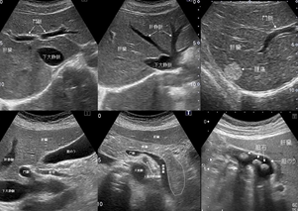

検査用のゼリーを塗りプローブ(探触子)を当てて観察します。

高周波数の音波を腹部にあて、臓器の状態を調べる検査です。心臓や肝臓、胆嚢、膵臓、腎臓、脾臓、乳腺の様子を観察することができます。検査は、X線検査でないので、「被ばく」もなく安全な検査です。